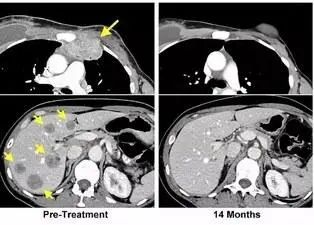

我们知道,乳腺癌早期确诊并积极接受治疗,仍有很高的治愈率,但对于结构工程师Judy来说,她的乳腺癌却发现在晚期,检查时已出现癌细胞转移扩散的情况,就连肝脏等重要器官上也有网球般大小的肿瘤,这样病重的Judy难道真的只剩下三个月的时间吗?

美国国家癌症研究所的免疫专家没有放弃Judy,他们对Judy实施了免疫疗法的治疗手段,而回输到Judy体内的900亿个免疫细胞也发挥作用,Judy体内的肿瘤细胞逐渐缩小甚至完全消失了!免疫疗法又再一次胜利!

黄色箭头为治疗前肿瘤位置,治疗结束14个月后复查显示:肿瘤完全消失